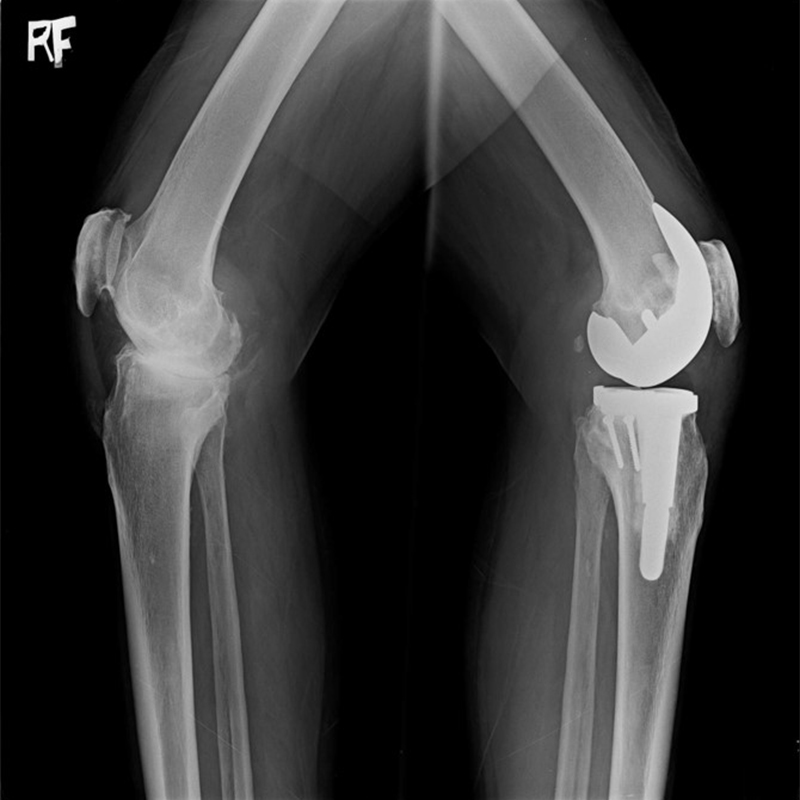

傳統全膝關節置換 首頁 案例分享 膝關節手術 傳統全膝關節置換 江女士 61歲 術前 術後 劉先生 83歲 術前 術後 70歲 柯先生 術前 術後 75歲 黃女士 術前 術後 77歲 羅女士 術前 術後